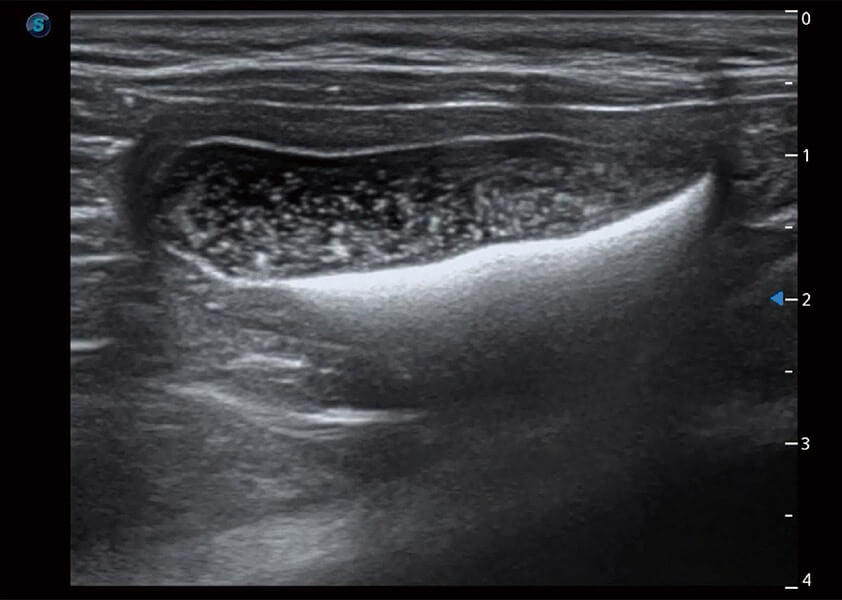

ProPet 60 作为一款高端台式动物超声设备,为动物医生的日常诊断提供了一系列贴合动物临床需求、解决临床实际问题的高级成像功能。凭借全系列高清探头,满足医生对腹部、心脏、生殖、浅表、肌骨等成像的所有需求,切实帮助您提升检查效率,提高诊断信心。

动物是人类最亲密的朋友和最值得信赖的伙伴。百老汇电子游戏官网也一直致力于探索动物专用的超声影像解决方案。 全新推出的ProPet系列,是百老汇电子游戏官网在动物超声影像智能化、专业化、精准化的一次跨越式革新。动物不能用言语来表述自己的不适,通过超声影像,ProPet系列搭建了动物医生与不同物种沟通的“桥梁”,为动物医生注入了“治愈之力”。